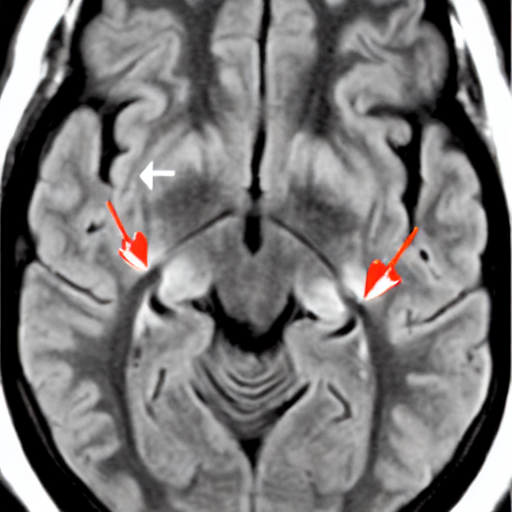

1. A 3-year-old child with visual difficulties. Axial FLAIR image show a supra-sellar lesion extending to the temporal lobes along the optic tracts (arrows) with moderate mass effect, compatible with optic glioma. FLAIR hyperintensity is also noted in the left mesencephalon from additional tumoral involvement

3_tumor